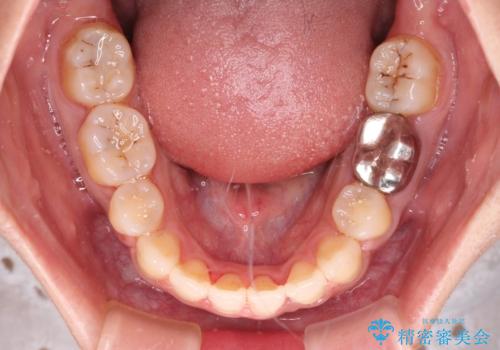

骨格的に下顎がやや前方にあるため、横顔のシルエットが著しく変化することはありませんでしたが、口元はスッキリと引っ込み、唇が閉じやすくなりました。